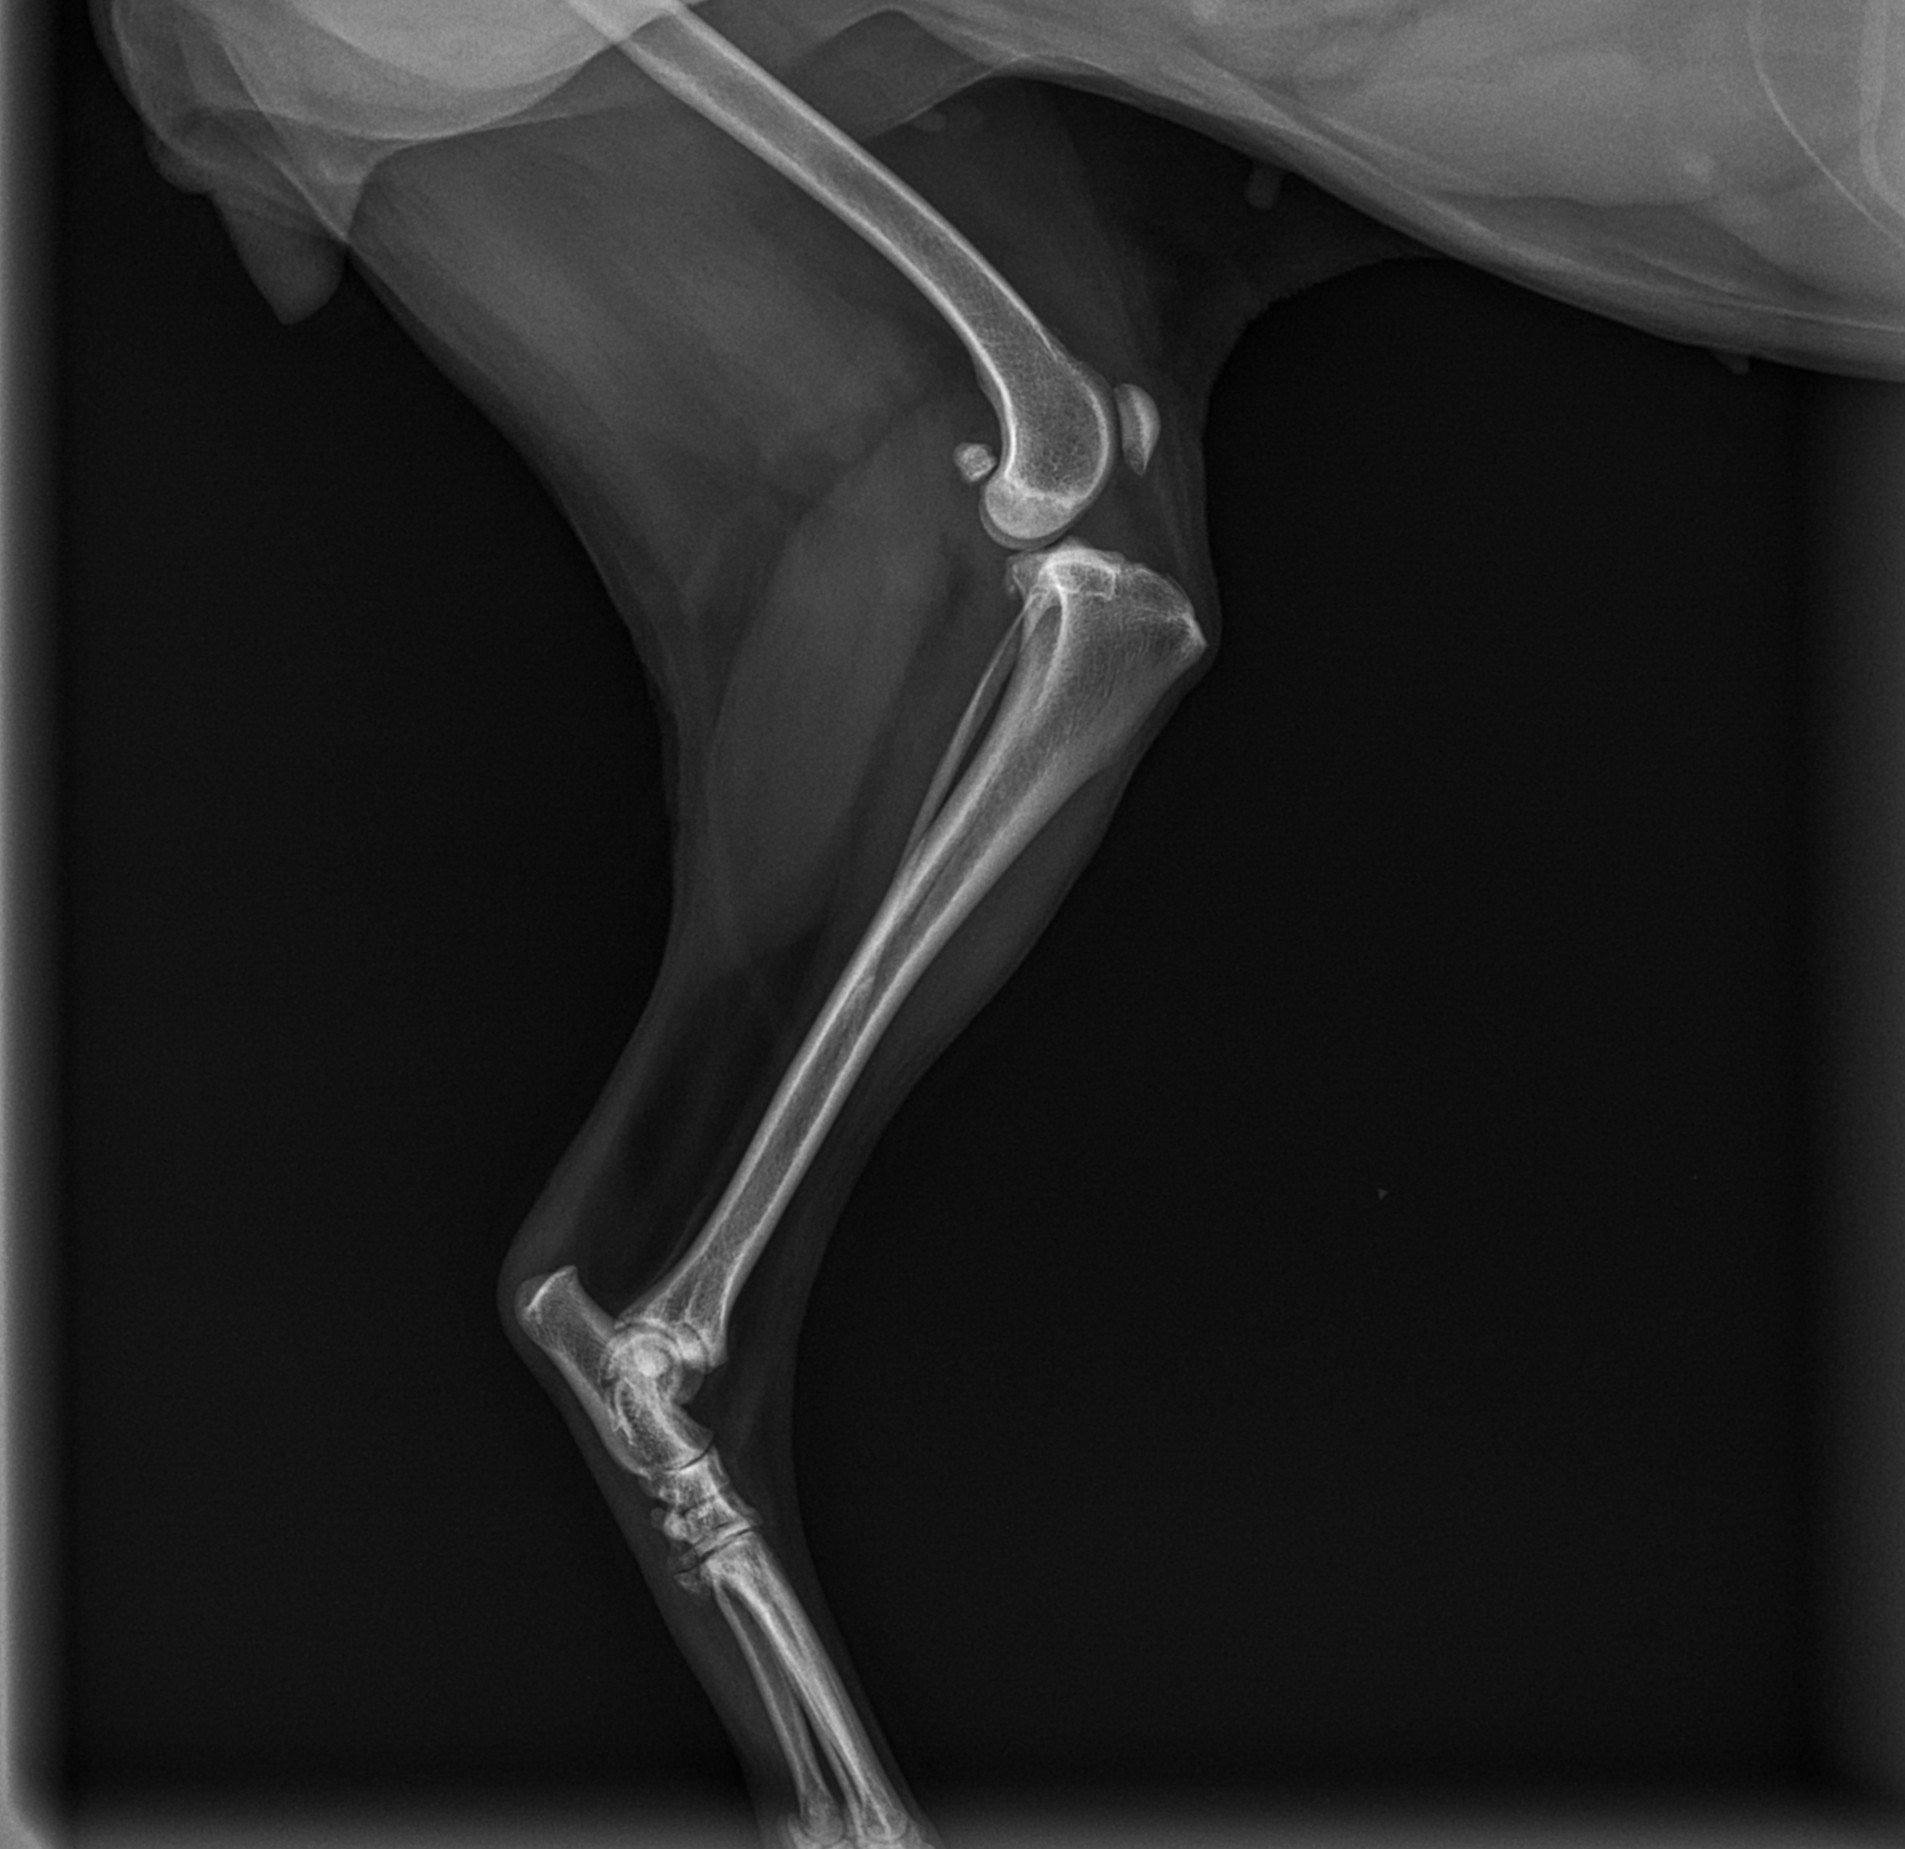

La radiología veterinaria es una herramienta fundamental dentro del diagnóstico por imagen y desempeña un papel clave en la detección, evaluación y seguimiento de múltiples patologías en perros y gatos. En Clínica Veterinaria La Graveta, contamos con radiología digital de alta calidad, que nos permite obtener imágenes nítidas y precisas de forma rápida, segura y con una mínima exposición a la radiación.

Gracias a la radiología veterinaria podemos evaluar de manera eficaz huesos, articulaciones, columna vertebral y órganos internos, facilitando un diagnóstico temprano y una correcta planificación del tratamiento más adecuado para cada paciente. Esta técnica es especialmente útil en casos de traumatismos, cojeras, problemas articulares, alteraciones óseas, enfermedades respiratorias, digestivas o cardiacas, así como en el control de procesos crónicos.